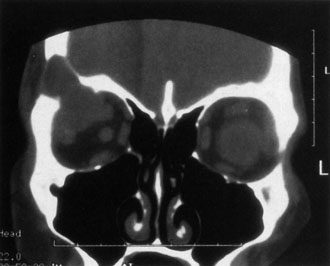

Investigations

If NFM is suspected, MRI should be ordered of the orbits and brain to exclude noncontiguous intracranial anomalies.93 Magnetic resonance imaging demonstrates the dilated cystic spaces with either a hypointense (lymphatic cyst) or hyperintense (hemorrhagic cyst) signal on T1-weighted images, and a hyperintense signal on T2-weighted images (Fig. 10, A&B).94Layering may be seen within the cysts if there has been a recent hemorrhage leaving unresorbed blood. The CT scans of patients with a deep NFM show low-density, poorly defined masses behind the orbital septum in the extraconal and intraconal spaces, which may indent the globe.3 Calcification within the mass (Fig. 11) and inhomogeneous enhancement of the rim and focal areas within the lesion may be seen that corresponds to abnormal endothelially lined channels.3 Enlargement of the bony orbit can occur, particularly with combined lesions.3,89 If the diagnosis is still unclear, ultrasonography can be performed. A cystic orbital mass is seen on B-scan. A-scan shows features of a solid, cellular tumor: low reflectivity, regular homogeneous internal structure, and marked sound attenuation through the mass.3,89 Standard pulsed Doppler ultrasound confirms no intrinsic flow within the lesions.